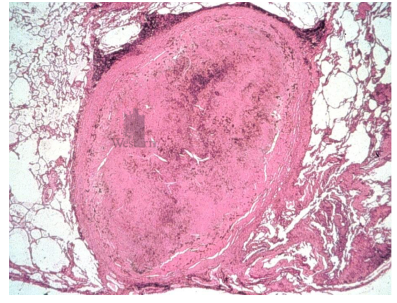

describe granulomatous inflammation

a type of chronic inflammation

• formation of granuloma = grain-like nodule

• granuloma is made of: macrophages with rim of lymphocytes and plasma cells

• often macrophages form giant cells (multinucleated)

• examples are: TBC, syphilis, fungal infxn, foreign body, etc.